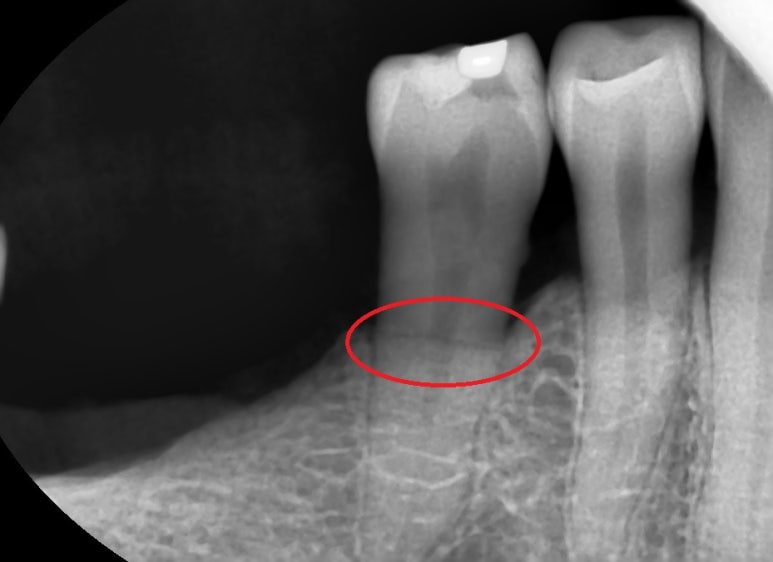

일반 분들은 이 선이 치아 신경인지 치조골인지, 치아주변인대인지

구별하기 쉽지 않을 것입니다.

어쨌든 치아가 머리부분만 살짝 깨진 것이 아니라

치아가 두동강이 났기 때문에

두 동강 중 위에 부분은 흔들리는 상태여서 발치기구로 잡자마자 바로 빠졌고

조금 남은 뿌리 부분은 통상의 발치 과정을 거쳐 발치 하였습니다